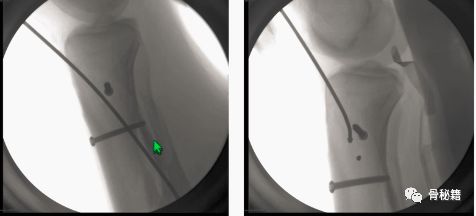

下来就是阻挡钉技术,阻挡钉主要作用就是缩窄髓腔,主要应用在干骺端的位置,想要防止骨折向哪边移位,就放在另外一边阻挡。

下图为例,防止骨折向右侧移位,置于左侧阻挡钉。注意!植入阻挡钉后,需要重新扩髓!

在进针的时候,也需要进行阻挡植入阻挡钉,近端主要是后方和侧方有时候都需要

注意用扩髓钻经过阻挡钉的时候,一定要轻柔

中上端的髓内钉,不是特别近端,还比较好植入,前后位移不大,但是容易在近端左右摆动。